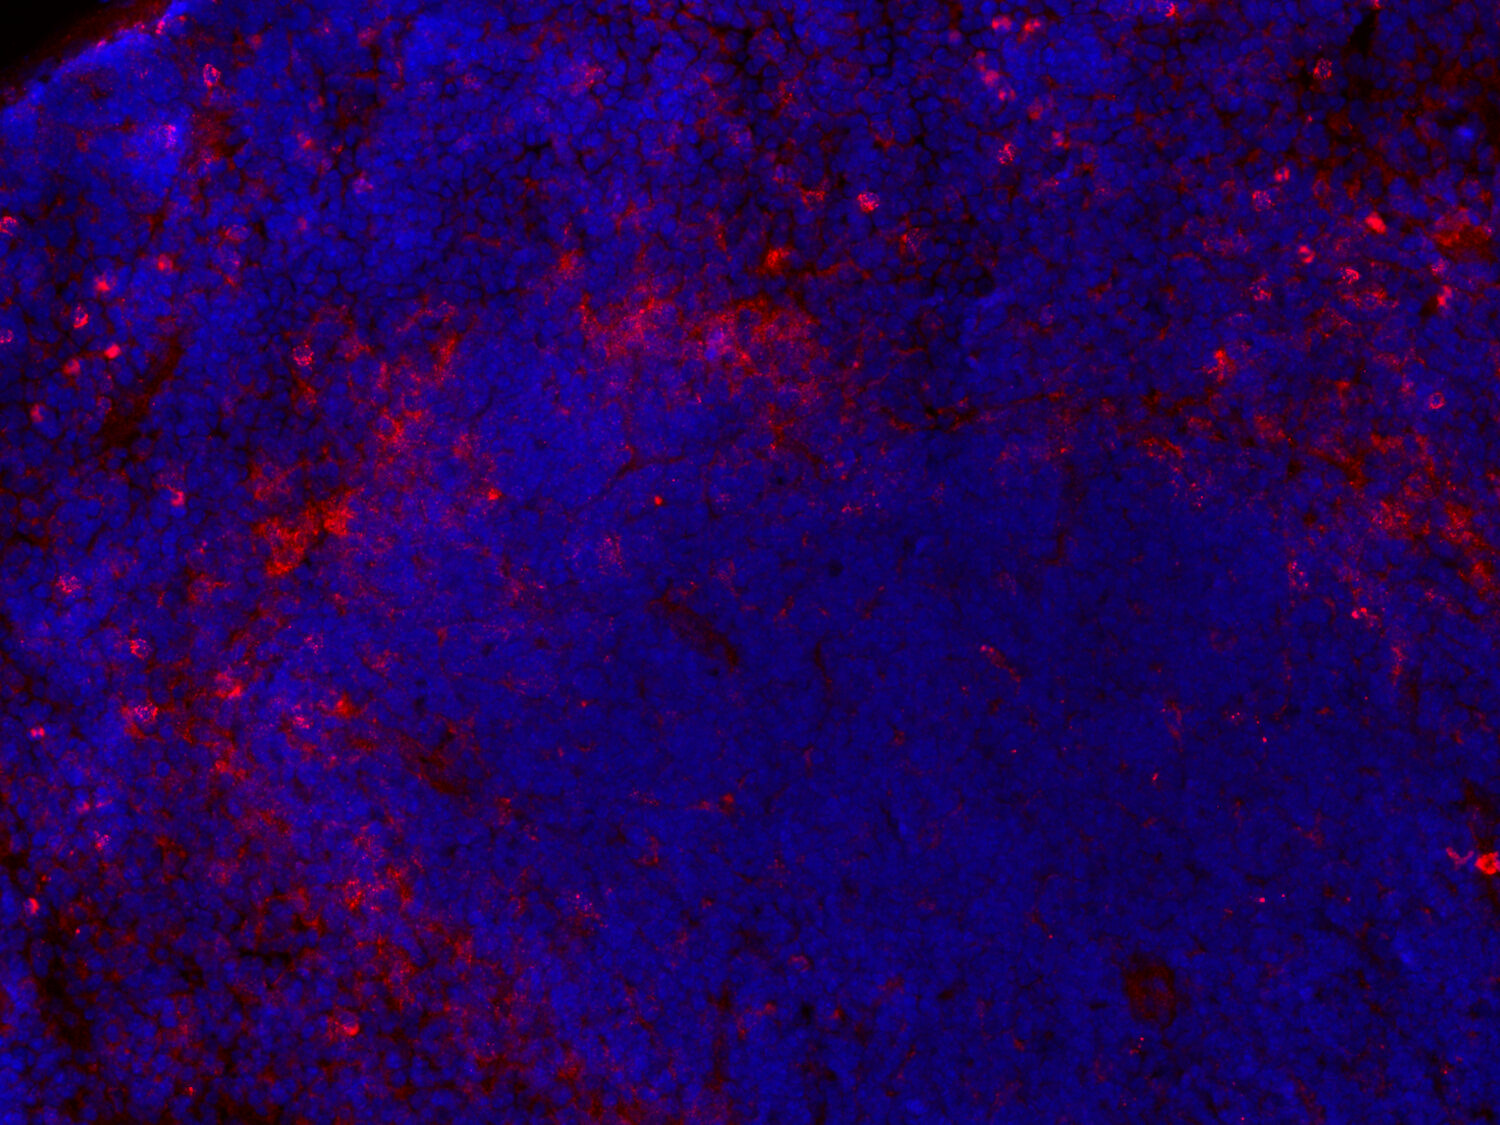

Galectin-3 is expressed in red pulp macrophages in the spleen

Galectin-3 (Gal-3, Mac-2) is a β-galactoside binding protein that is predominantly located in the cytoplasm and shuttles into the nucleus. In addition, it is secreted to the cell surface and into biological fluids. Depending on its localization, it exerts pleiotropic biological functions like cell growth, cell differentiation, inflammation, fibrogenesis, migration, apoptosis, and host defense (1). It is also involved in cancer pathogenesis, proliferation, and spreading of metastasis (2). Galectin-3 is highly expressed in the covering epithelia of the digestive tract and the urinary system (3) and plays important roles in the organization of renal and intestinal cells. Furthermore, Galectin-3 has been identified in a variety of other cell types including fibroblasts, keratinocytes, granulocytes, dendritic cells, and macrophages (2). Galectin-3 is expressed by certain tissue-resident macrophages such as Kupffer cells in the liver, red pulp macrophages in the spleen, and alveolar macrophages in the lung (3). In the brain, Galectin-3 is abundant in activated microglia but not expressed in resting cells. Following brain injury, Galectin-3 triggers anti-inflammatory properties of microglia (4). In Alzheimer’s disease, Gal-3 expression is strictly associated with microglial cell activation around Aβ plaques. In stroke, Gal-3 was found to be expressed primarily in proinflammatory microglial cells (5).